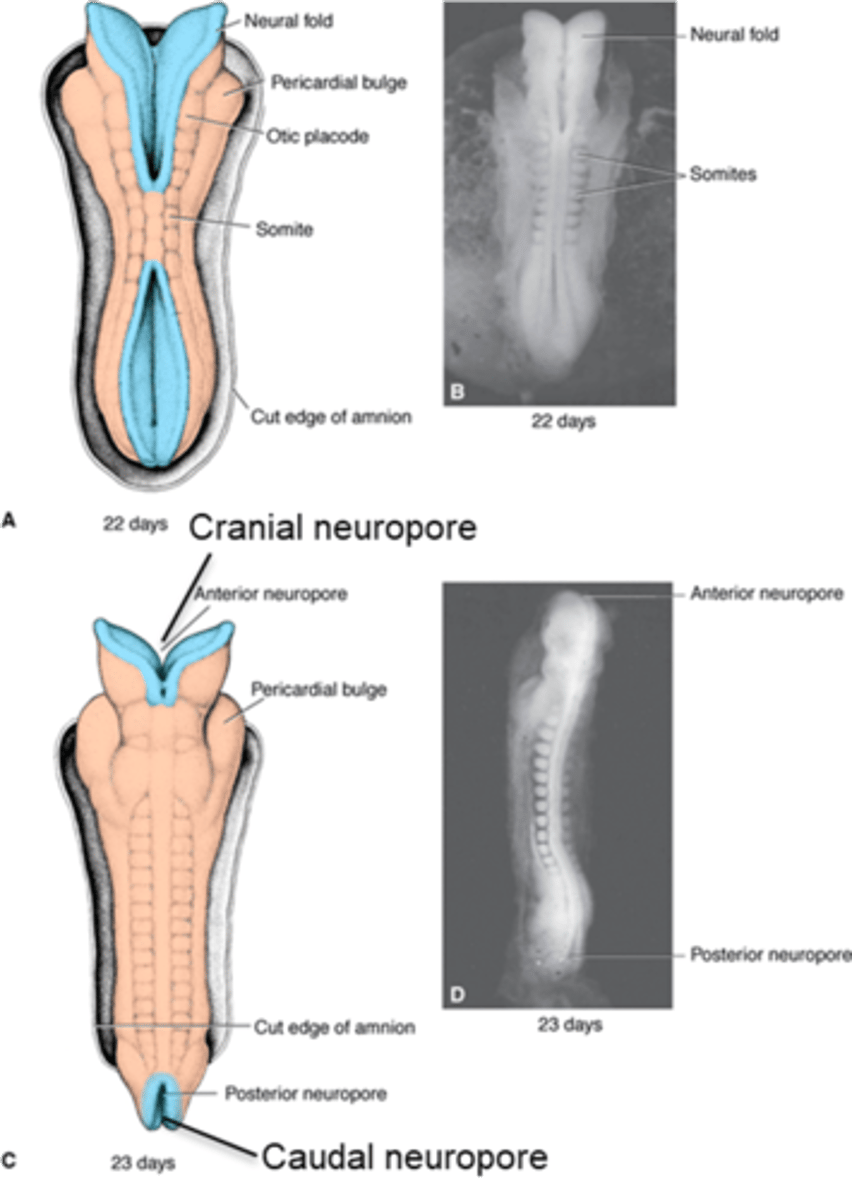

the fusion of the neural folds begins in the __________ region then proceeds ___________ and __________ to form the neural ________

cervical, cranially, caudally, tube

the (caudal/cranial) neuropore will normally close on day ____ before the (caudal/cranial) neuropore which closes on day ____

cranial, 25, caudal, 28

the narrow (caudal/cranial) portion of the neural tube will form the spinal cord while the broad (caudal/cranial) portion forms the brain vesicles

caudal, cranial

what neural tube defect is the most severe and caused by the failure of cranial neuropore to close leading to the absence of the major portion of skull and cerebral hemispheres?

anencephaly

what neural tube defect is caused by the failure of the caudal neuropore to close and varies in severity (like meningocele and myelomeningocele)?

spina bifida